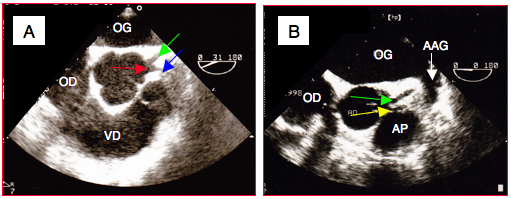

10. Vue bicave modifée pour la valve tricuspide MO 70° (Vidéo et Figure 25.64)

Figure 25.64 : Vue bicave modifiée pour la valve tricuspide à 60-90°. Vue schématique et image ETO. AP: artère pulmonaire (ou chambre de chasse du VD). VCS: veine cave supérieure. VCI: veine cave inférieure.

9. Vue chambre d’admission – chambre de chasse du VD MO 60° (Vidéo et Figure 25.63)

Figure 25.63 : Vue chambre d’admission – chambre de chasse (inflow-outflow) du VD rétrocardiaque mi-oesophage à 60°. A: plan de coupe. B: Déroulement du VD. FP : feuillet postérieur de la valve tricuspide. FA : feuillet antérieur de la valve tricuspide. Ao : valve aortique (ouverte). VP : valve pulmonaire. CCVD : chambre de chasse du VD. PAVD : paroi antérieure du VD. C: vue ETO à 60°. D: vue centrée sur la chambre de chasse du VD et le long-axe de la valve pulmonaire (flèche jaune); présence d'un cathéter pulmonaire de Swan-Ganz dans le VD (flèche verte).